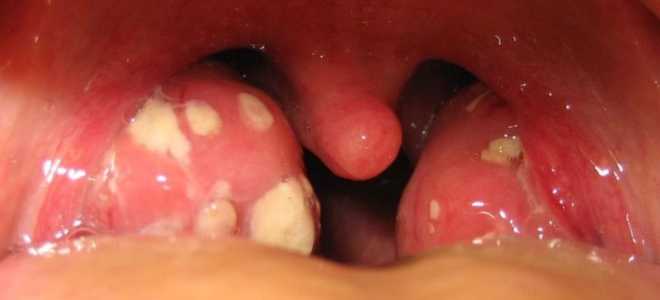

Гнойники на миндалинах как лечить

Гнойники на миндалинах как лечить Как убрать гнойники с миндалин Гнойники на миндалинах, налёт разного цвета, красное горло – всё...